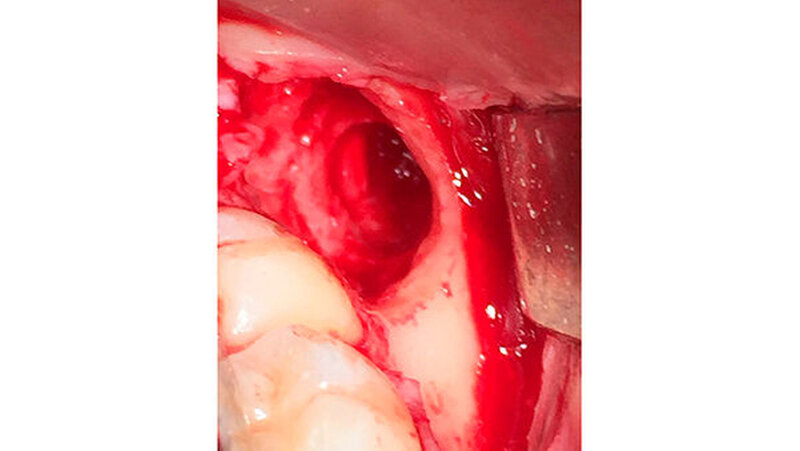

Die Zähne 28 und 18 wurden nach Aufklappung und Osteotomie schonend entfernt. Eine Mund-Antrum-Verbindung konnte intraoperativ ausgeschlossen werden. Für regio 48 wurde eine sulkuläre Schnittführung ab regio 43 gewählt, da eine eventuelle Verplattung vorgesehen war. Intraoperativ ließ sich der Zahn 48 komplikationslos in toto entfernen und die Alveole war klinisch knöchern intakt, der Nerv nicht verletzt (Abbildung 4).